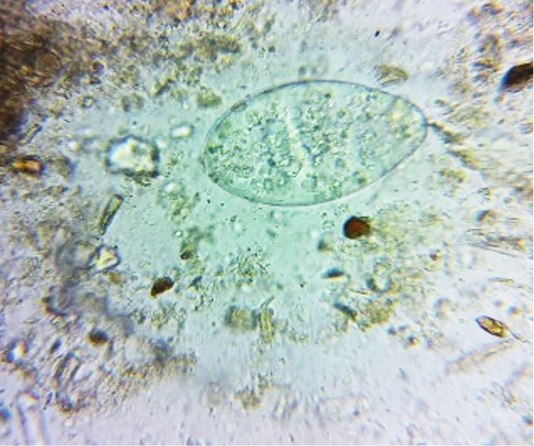

Figure 4

Faeces examination by sedimentation method showed Amphistome eggs (x 400) in three animal.